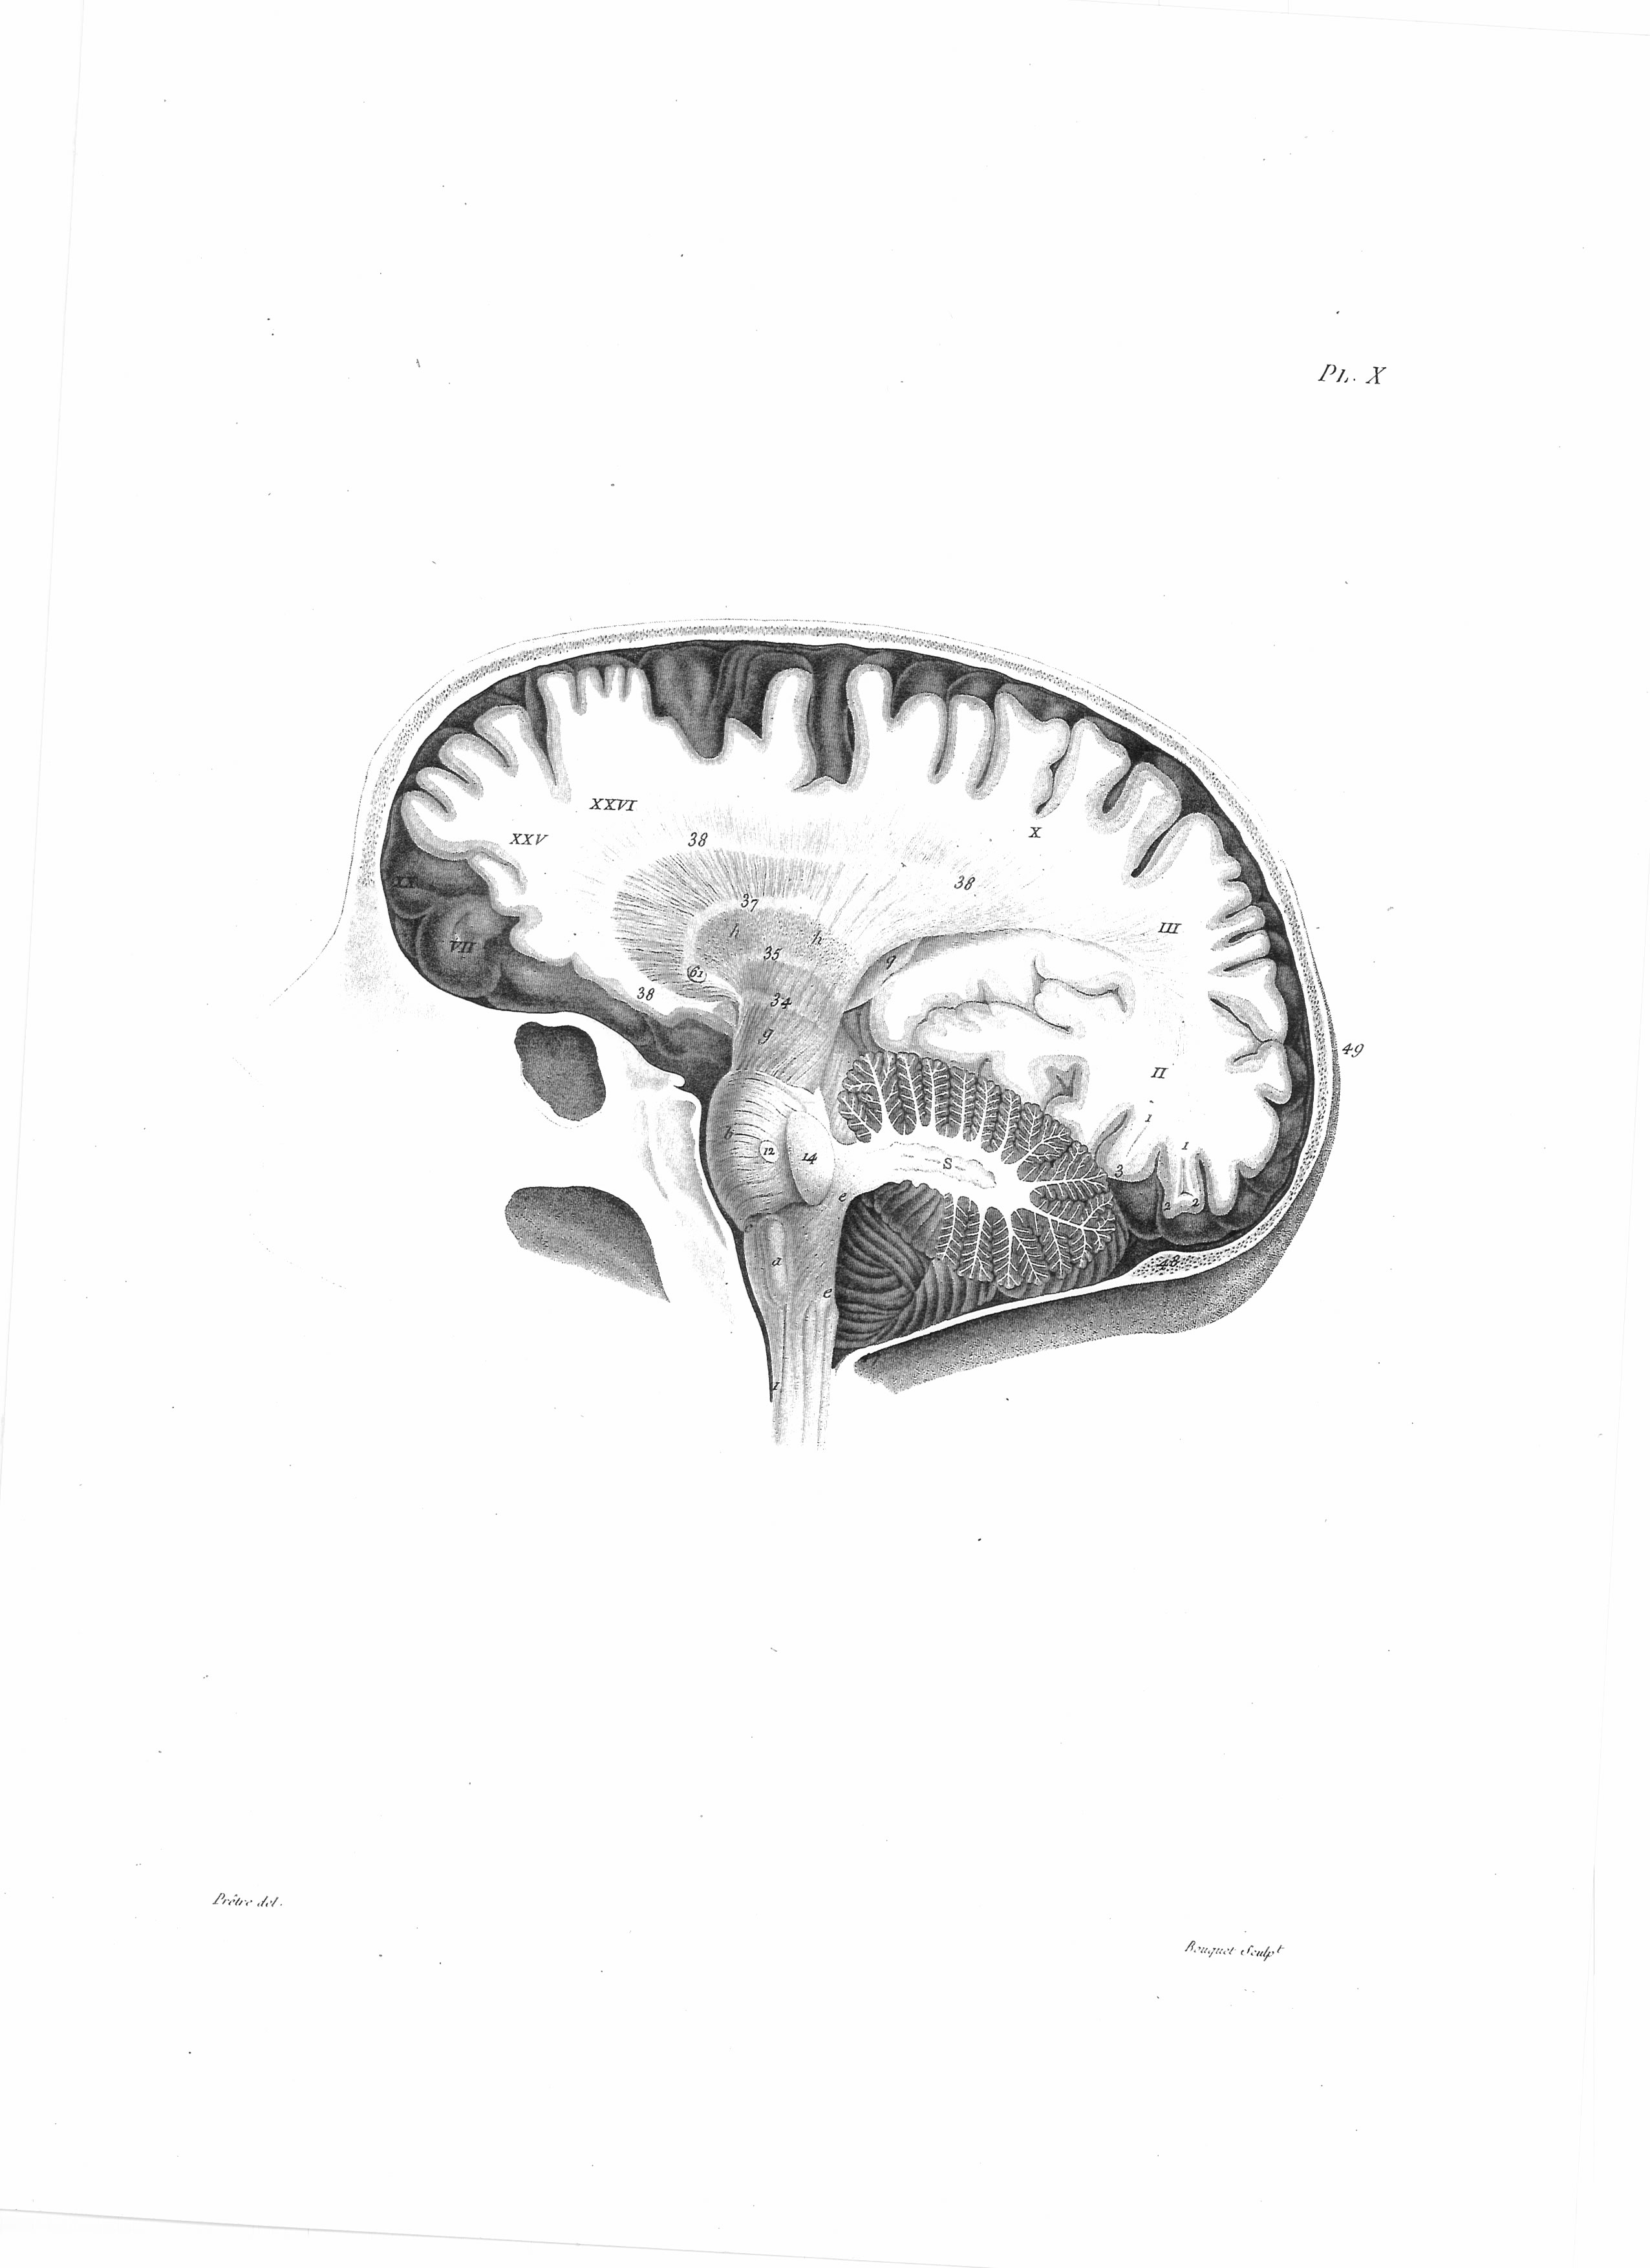

Gall, F. J. (1818). Anatomie et physiologie du système nerveux en général, et du cerveau en particulier, Avec des observations sur la possibilité de reconnoître plusieurs dispositions intellectuelles et morales de l´homme et des animaux, par la configuration de leurs têtes.

Librairie Grecque-Latine-Allemande, Vol. 3, I-XXXV u. 1-379 100 planches.